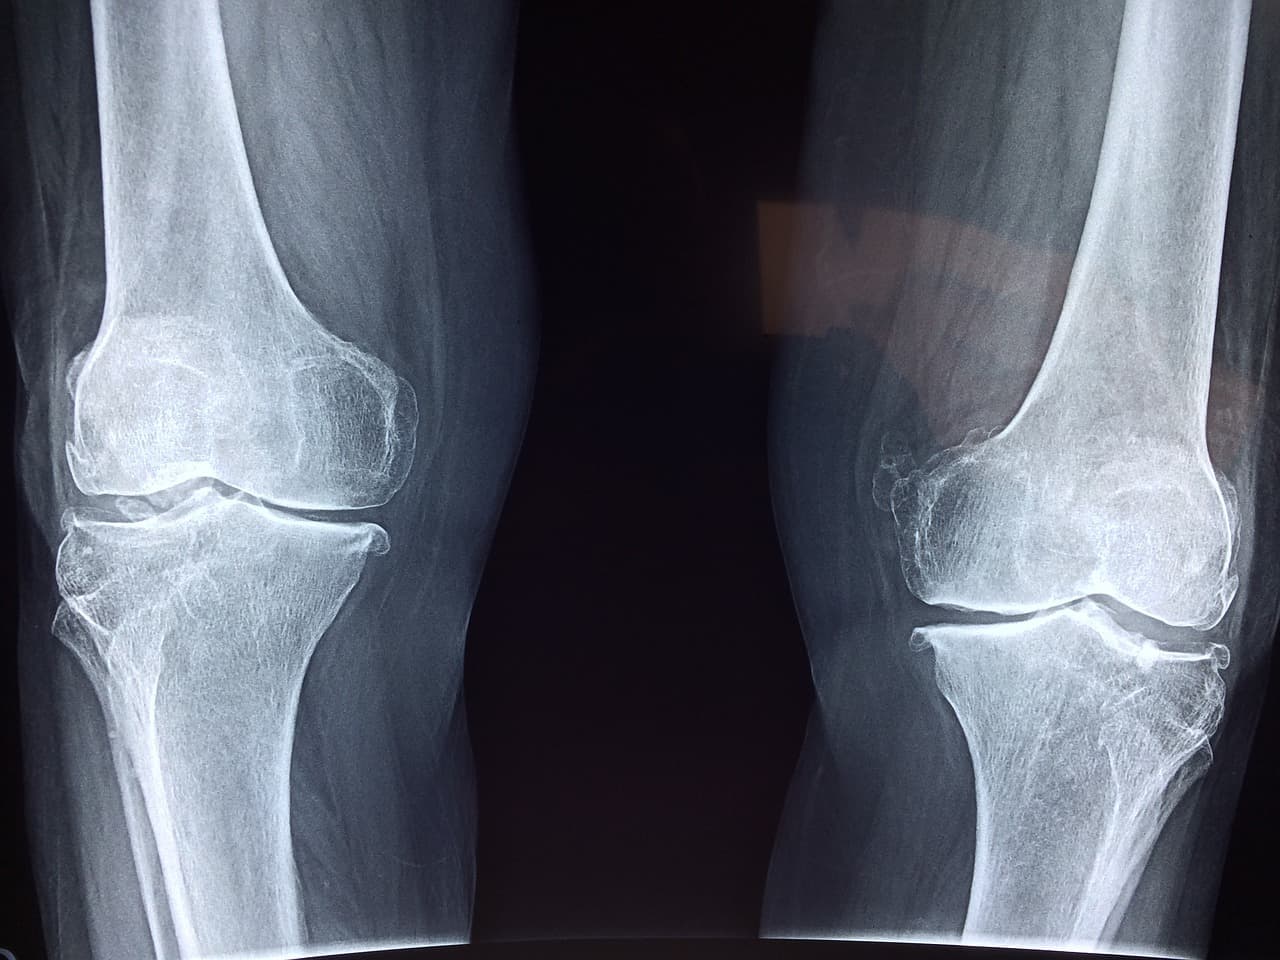

나이가 들수록 소중함을 깨닫게 되는 것 중 하나가 바로 관절 건강입니다. 무릎, 어깨, 허리 등 관절은 매일 무수히 많은 움직임을 지원하는 역할을 하면서도, 오랫동안 침묵하다가 문제를 드러내곤 합니다. 이러한 관절 건강을 지키기 위한 방법으로 주목받고 있는 것이 바로 글루코사민입니다.

관절은 소모되는 속도가 회복되는 속도보다 빨라질 때 문제가 발생합니다. 특히 무릎과 같은 하중이 많이 가해지는 관절은 더욱 그렇습니다. 글루코사민은 연골을 구성하는 데 필요한 영양분을 공급하고, 관절 내 염증을 줄이는 데 도움을 줄 수 있습니다.

글루코사민은 우리 몸의 연골, 인대, 힘줄 등의 구성 요소에 자연적으로 존재하는 아미노당의 일종입니다. 특히 관절 부위의 윤활과 충격 흡수를 담당하는 연골 조직을 구성하는 데 중요한 역할을 합니다. 하지만 나이가 들면서 체내 글루코사민 생성량이 감소하게 되고, 이로 인해 관절 통증이나 연골 손상이 나타나기 쉽습니다.